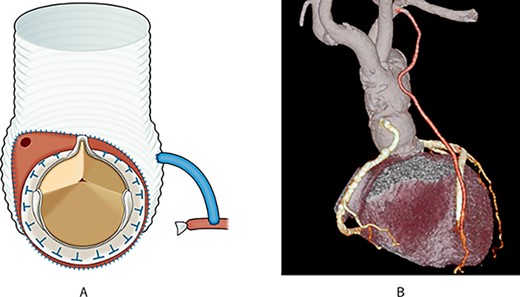

We considered performing the Bentall-De Bono operation; however, due to preoperative circulatory deterioration, we decided to perform hemi-root replacement while preserving the left sinus of Valsalva and the ostium of the LCA, resection of the right and non-coronary sinus of Valsalva, translocation of the RCA with vein graft and aortic valve replacement (AVR), as shown in Fig. 2 and Supplementary Video 1.

Post-operative schema and 3D CT; (A) the aortic root was resected diagonally, and AVR was performed; next, the vascular graft was anastomosed to the aortic root; finally, the right coronary artery was translocated using an SVG; (B) post-operative 3D CT showed that the pseudoaneurysm disappeared, and all grafts were patent.

First, the aortic root was diagonally resected with sufficient debridement of the infected tissues. Thereafter, AVR was performed, and a 26-mm J graft 1 branched (Japan Lifeline Inc, Tokyo, Japan) was anastomosed to the aortic root. Finally, the RCA was translocated using an SVG.